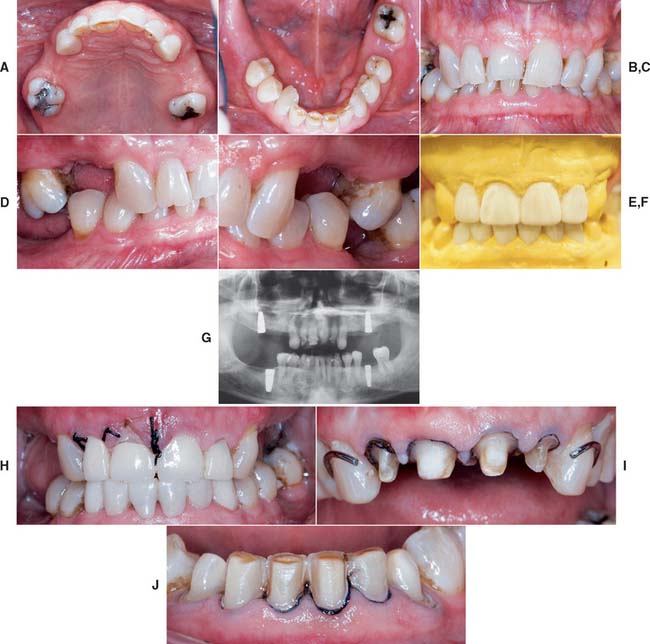

After placement and cementation of a fixed dental prosthesis (FDP), patient treatment continues with a carefully structured sequence of postoperative appointments designed to monitor the patient’s dental health (Fig. 32-1), stimulate meticulous plaque control habits, identify any incipient disease, and introduce whatever corrective treatment may be needed before irreversible damage occurs.

Fig. 32-1 Treatment after placement of multiple restorations. To ensure tissue health and long-term success, proper oral hygiene is mandatory.

Patients with cast restorations should attend recall visits at least every 6 months. Less frequent recall may lead to oversight of recurrent caries or the development of periodontal disease. Patients who have been provided with extensive fixed prostheses (Fig. 32-6) need more frequent recall appointments, particularly when advanced periodontal disease was present. The appointments can be coordinated by the restorative dentist or the periodontist. To ensure treatment continuity, it is imperative to establish in advance who will assume primary responsibility for coordinating recall appointments.

Fig. 32-6 Patients who have received extensive treatment of this nature require more frequent follow-up care.